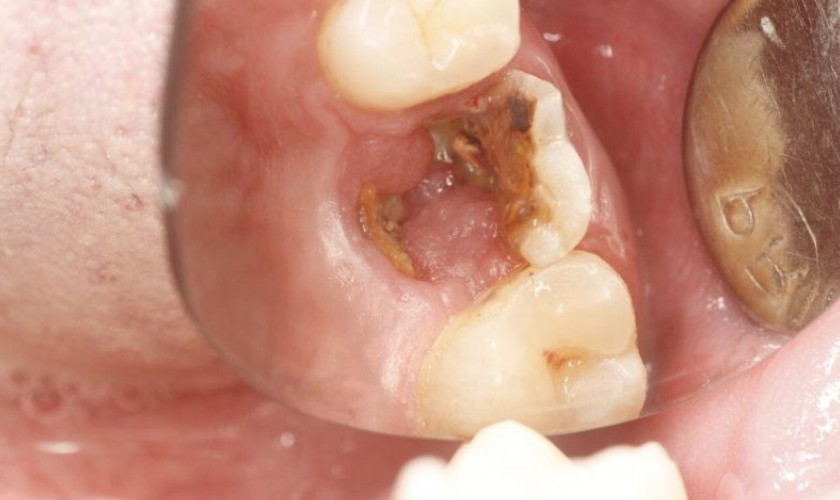

Răng hàm bị sâu chỉ còn chân điều trị như thế nào?

Răng hàm bị sâu chỉ còn chân gây khó khăn khi ăn uống, thậm chí còn gây đau nhức, khó chịu, ảnh hưởng đến sinh hoạt hàng ngày của người bệnh. Cách khắc phục tình trạng này như thế nào? Hãy cùng tìm hiểu qua những thông tin trong bài viết sau.